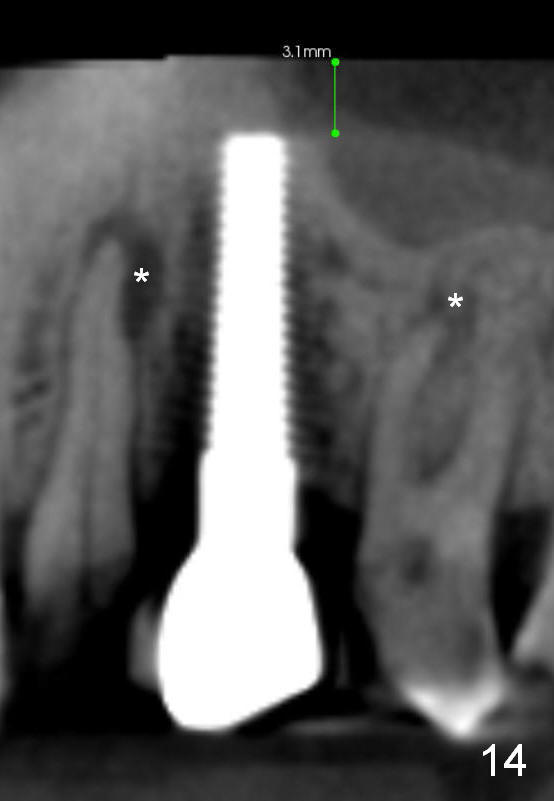

Eight months post cementation, CBCT shows periapical infection of the neighboring teeth (Fig.14 *).  There is still apical bone for a longer implant (Fig.14 green line, Fig.15 *).  The implant functions 1.5 years post cementation. When the implant at the lower bicuspid fails, the patient reveals that he is a diabetic.  The latter is the main reason of delayed healing.